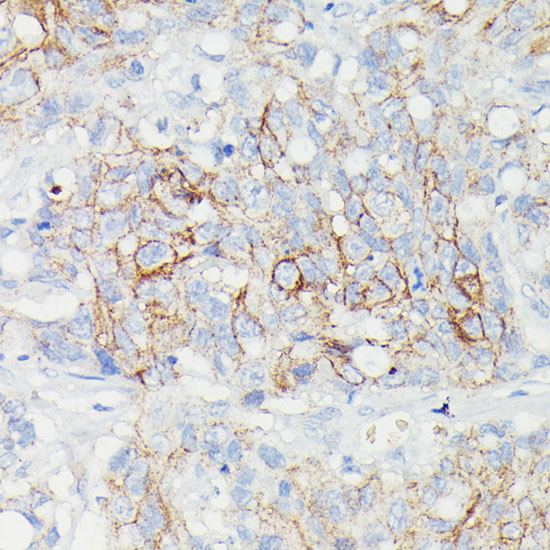

Immunohistochemistry of paraffin-embedded Human lymph node tumors using SLC14A1 at dilution of 1:100 (40x lens).